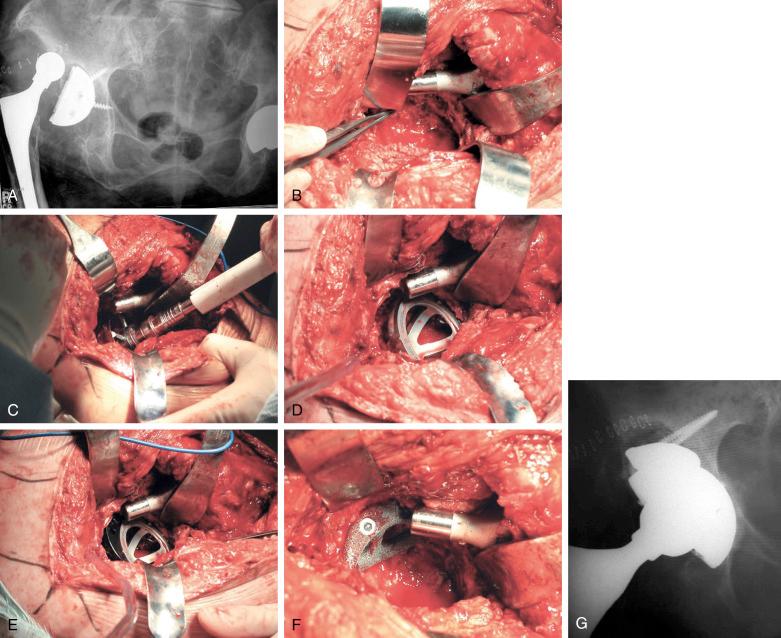

A 90-year-old woman presented with a failed acetabular component and superior segmental bone loss ( Fig. 55.2 ).

FIGURE 55.2, A, Anteroposterior radiograph of a 90-year-old woman with a failed acetabular component and substantial bone loss. B, Intraoperative photograph of the defect. C, Reaming of the acetabulum. D and E, Trialing with the acetabular component and an augment. F, The augment before placement of the acetabular component. G, Postoperative anteroposterior radiograph.